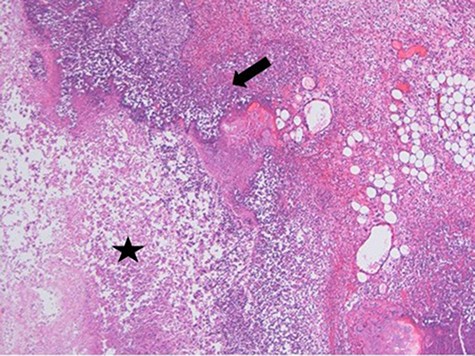

At laparoscopy, there were very dilated and inflamed loops of small bowel, and the appendix appeared normal macroscopically. Due to the extent of bowel dilatation obscuring adequate laparoscopic vision and assessment, decision was made to convert to an open procedure. At laparotomy, there was a nodular mass in the jejunal mesentery measuring about 3 cm in diameter with central necrotic tissue (Fig. 1). As it was adherent to the surrounding bowel, a limited small bowel resection was performed (Fig. 2) with side to side stapled anastomosis. Histology revealed normal small bowel wall with a mesenteric nodular mass comprised of architecturally normal pancreatic tissue including exocrine ducts and endocrine islets of Langerhans (Figs 3–5), consistent with a diagnosis of mesenteric heterotopic pancreas. His post-surgical recovery was uneventful and was discharged after five days of stay in hospital. He had an outpatient magnetic resonance imaging (MRI) of the pancreas which reviewed normal pancreas tissue, and he was followed up three months post-surgery.

Necrosis (star) and acute inflammation with the presence of stromal neutrophils (arrow) within the mesenteric mass (H&E stain, x100).